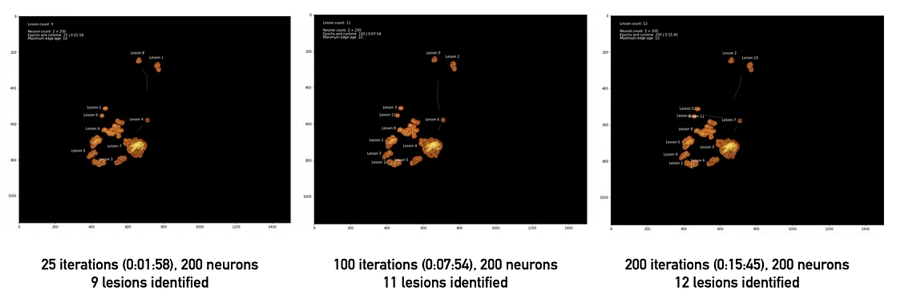

终端神经元数量越多,形状近似越准确,但运行时间也越长(左:200 个神经元,右:1,000 个神经元)。

使用 GNG 计算聚类簇时,一些设置至关重要。特别是,值得从大量初始神经元开始。在第 1 部分中提到的图像矢量量化示例中,我们从两个神经元开始。这样做的结果是一个图,该图在大多数时间将保持完全连接(回想一下,对于 GNG 来说,生成新神经元比删除现有神经元要容易得多)。这是一个问题,因为我们依靠计算断开连接的子图来确定不同病变的数量。最简单的解决方案是创建大量初始神经元(几千个,即比预期的不同簇数量多 2-3 个数量级)。虽然延长了训练时间,但一段时间后确实会导致分割越来越准确——最重要的是,与初始神经元数量较少的分割不同,它们不太可能具有需要多次迭代才能分离的连接段。

在大量迭代中使用相同的设置可以更好地分离近距离神经元

基于生长神经气体的模型不仅擅长矢量量化,还能从所有数据点的一小部分创建可行、可理解的数据表示。它们还可以找到未知数量的连贯拓扑。如果有时间收敛,这些模型不仅可以识别不同拓扑的数量,还可以量化它们的相对和绝对面积。